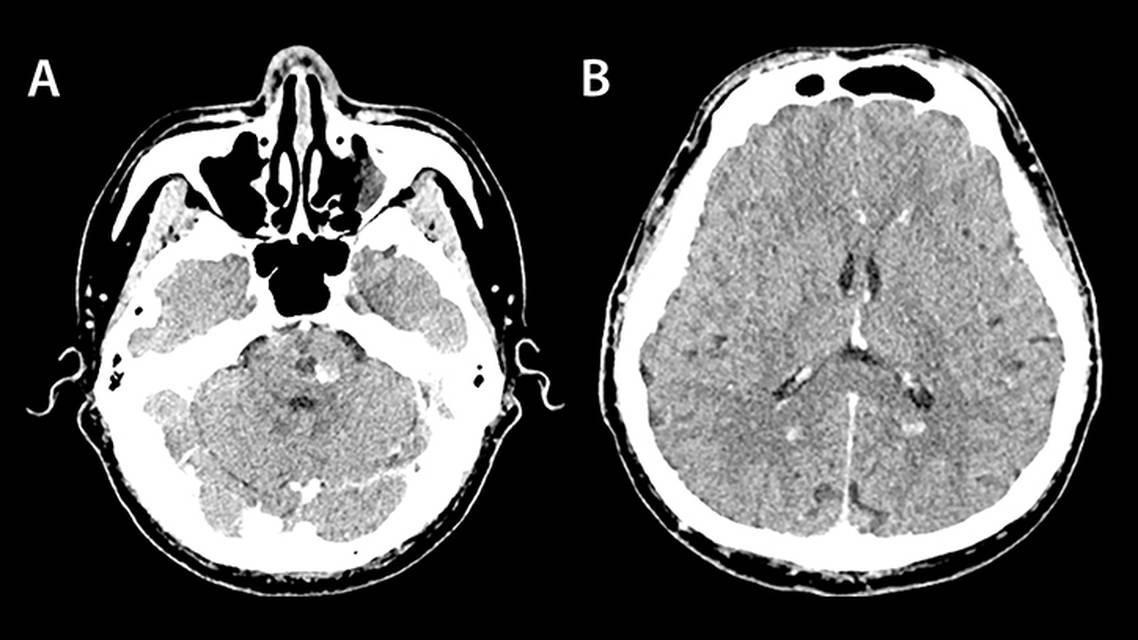

Head CT (Figure 1) showed multiple nonenhancing, ill-defined hyperdense lesions in the cerebral hemispheres, cerebellum, and pons with prominent focal calcification at the pons.

On head CT, FCCM may manifest as multiple calcified intracranial lesions easily mistaken for neurocysticercosis, a parasitic infection caused by T. solium, endemic in Asia and other regions.4 Lesions of CCM may be solitary or multiple, but the presence of multiple lesions increases the likelihood of FCCM.5,6 People with FCCM may also have vascular lesions outside the CNS including retinal vascular malformations (eg, retinal cavernoma or, rarely, choroidal hemangioma) and cutaneous lesions (eg, café-au-lait lesion, capillary malformations, angiokeratoma, hyperkeratotic cutaneous capillary venous malformation, or venous malformations).7-9

Although CT is more readily available than MRI in many parts of the world, fewer lesions are visible on CT, leading to underestimation of lesion load. It is also difficult to distinguish calcified cavernomas from calcified-nodular stage of neurocysticercosis using CT alone.4,11 The best practice standard for neuroimaging evaluation of CCM is brain MRI with GRE or susceptibility-weighted imaging (SWI) sequences.5< In the case presented, the relatively large classic popcorn appearance of lesions with mixed signal intensity centrally at pons on MRI favored the diagnosis of CCM over neurocysticercosis, which typically presents with more uniform and smaller lesions.10,11